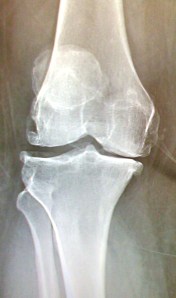

I went to my ortho doctor recently and he did some new xrays. If you’ve ever wanted to see what advanced arthritis of the knees looks like- here you go!

I took a picture of my xrays with my phone. As you can see, I’m bone on bone.

And see those little hooks on the ends of my bones? Those are calcium deposits from the arthritis. The round things are my knee caps. Apparently they are higher than they should be. Looks like I’ve got coasters on my thighs!